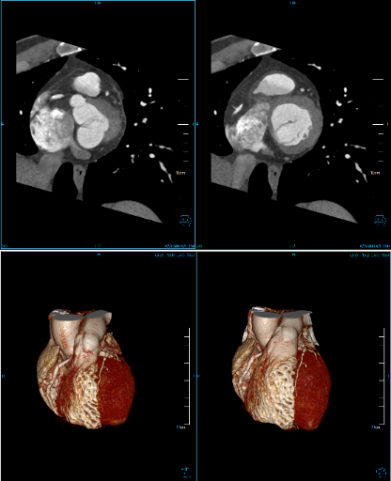

Cardiac Function Analysis

Analyze a variety of heart functions

• Left ventricular volumes Ejection fraction

• Left ventricle wall motion and thickening

• 4D Rendering

One Station Cardiac Diagnosis Analysis